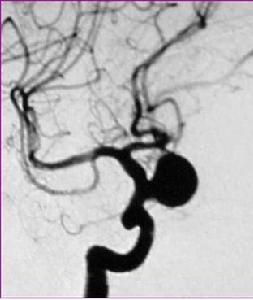

3.腦血管造影是確診顱內動脈瘤必須的檢查方法,對判明動脈瘤的準確位置、形態、內徑、數目、血管痙攣和確定手術方案都十分重要。DSA更為清晰。,經股動脈插管全腦血管造影,可避免遺漏多發動脈瘤。病情在三級以下,腦血管造影應及早進行,三級和三級以上病人可待病情穩定後,再行造影檢查。及早造影明確診斷,儘快手術夾閉動脈瘤,可以防止動脈瘤再次破裂出血。首次造影陰性,可能因腦血管痙攣而動脈瘤未顯影,高度懷疑動脈瘤者,應在3個月後重複造影。

顱內動脈瘤2.局灶症狀取決於動脈瘤的部位、毗鄰解剖結構及動脈瘤大小。動眼神經麻痹常見於頸內動脈-後交通動脈瘤和大腦後動脈的動脈瘤,表現為單側眼瞼下垂、瞳孔散大,內收、上、下視不能,直、間接光反應消失。有時局灶症狀出現在蛛網膜下腔出血之前,被視為動脈瘤出血的前兆症狀,如輕微偏頭痛、眼眶痛,繼之出現動眼神經麻痹,此時應警惕隨之而來的蛛網膜下腔出血。大腦中動脈的動脈瘤出血如形成血腫;或其他部位動脈瘤出血後,腦血管痙攣腦梗死,病人可出現偏癱,運動性或感覺性失語。巨大動脈瘤影響到視路,病人可有視力視野障礙。動脈瘤出血後,病情輕重不一。為便於判斷病情,選擇造影和手術時機,評價療效。